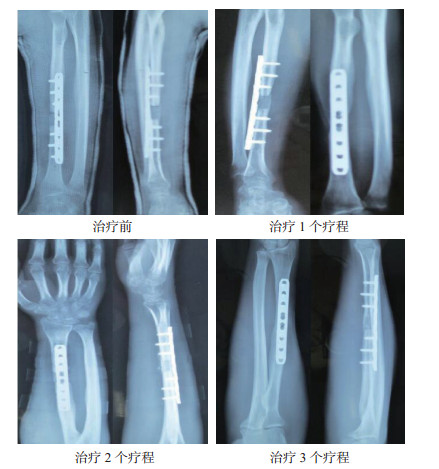

2 结果治疗前患者骨折断端处可见有清晰的骨折线,治疗1个疗程患者骨折断端骨痂生成,治疗2个疗程患者骨折断端处骨折线模糊,治疗3个疗程患者骨折断端处有大量的骨痂生成,骨折线消失,并形成骨链接。见图 1。

| 图 1 骨折延迟愈合患者治疗前后骨折部位变化 |